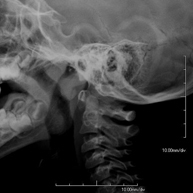

- RX Columna cervical

Técnica mediante la cual, utilizando rayos X, se obtienen imágenes de la columna cervical para su estudio. Indicaciones: traumatismo, contractura cervical, dolor articular.

Técnica mediante la cual, utilizando rayos X, se obtienen imágenes de la columna cervical para su estudio. Indicaciones: traumatismo, dolor cervical.